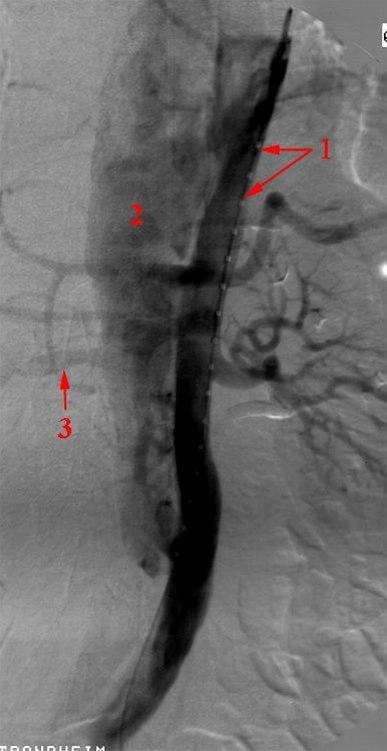

Aortadisseksjon (angiografi)

Angiografi

Aortadisseksjon

1. Kateter i det ekte lumen

2. Falskt lumen

3. Høyre nyrearterie som avgår fra det falske lumen